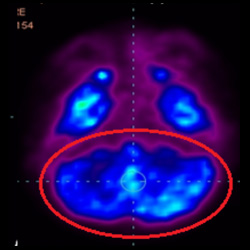

干細胞治療腦癱后改善的客觀放射學證據

細胞治療后,藍色和黑色區域減少,并且看到更活躍的區域。這表明損傷減少并改善了大腦功能。

細胞治療前 PET CT 掃描顯示神經組織中的藍/黑色區域,表明腦癱引起的大腦損傷。

這證明細胞療法是治療腦癱兒童安全有效的方法。細胞療法可以更新大腦損傷的核心,并且可以通過 PET CT 掃描來監測大腦的改善情況。這些細胞療法與標準治療一起促進腦癱兒童的生長和改善。